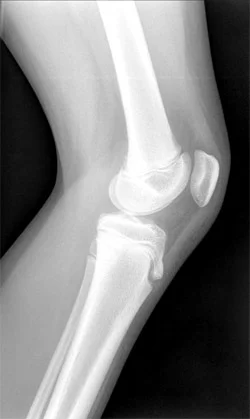

Knee pain in older adults - Don't say its "Just My Arthritis"

Sometimes it is easy to say, "that's just my arthritis" and accept pain as a part of life. But here at Thornleigh Performance Physiotherapy, we take an innovative and evidence based approach to improving your pain free function.

Knee pain in younger athletes

Knee pain is a common complaint we see here at Thornleigh Performance Physiotherapy. In the younger athlete we need to consider Osgood Schlatter Disease as a potential diagnosis.